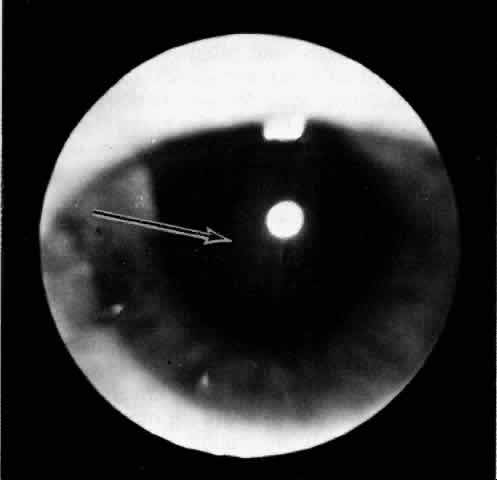

Fig. 5. Flat ciliochoroidal effusion. The ora serrata is visible without scleral depression in a patient with Schepens-Brockhurst syndrome. The arrow indicates the ora bay.

The presence of certain clinical characteristics may assist in the diagnosis of a ciliochoroidal effusion (Table 1). One clinical feature is choroidal edema. Choroidal edema may resemble a retinal detachment to a hasty observer; however, darkness of the uvea, lack of tremulousness, and normal retinal vessels indicate a probable uveal process (Fig. 1). The effusion may extend under the pars plana, allowing visualization of the ora serrata without scleral depression (Fig. 2).9 As shown in Figure 2, the surface of the elevation is convex and smooth, with a solid appearance and a homogeneous grayish color. A shallow anterior chamber and a low intraocular pressure may also suggest the diagnosis. Myopia in the presence of anterior displacement of the lens-iris diaphragm may be another diagnostic clue.10,11